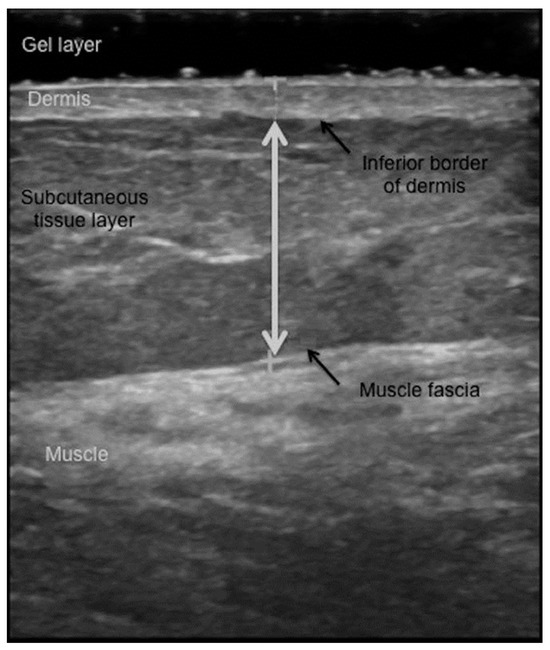

- Toomey, C.; McCreesh, K.; Leahy, S.; Jakeman, P. Technical considerations for accurate measurement of subcutaneous adipose tissue thickness using B-mode ultrasound. Ultrasound 2011, 19, 91–96. [Google Scholar] [CrossRef]